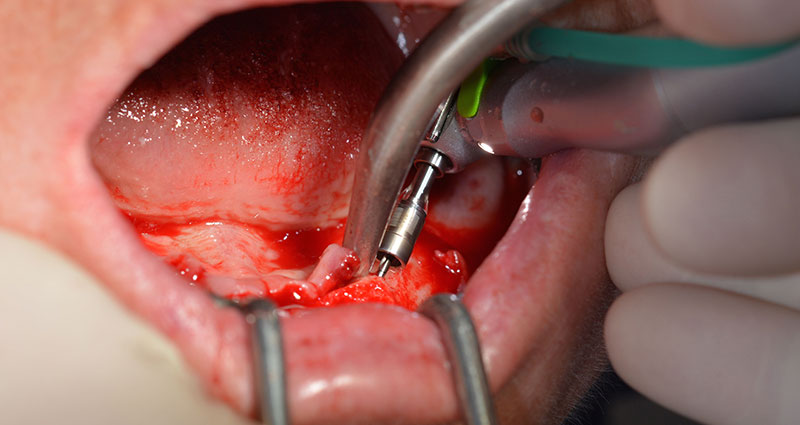

Dopo aver rimosso la dentatura residua dalla mandibola, la cresta alveolare viene esposta da 37 a 47.

Prima di tutto, è stato individuato il forame mentoniero come limite della struttura anatomica. Successivamente, l'osso corticale della cresta è stato lisciato con un manipolo e una fresa larga a rosetta (Fig. 4).